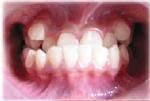

反頜, 俗稱“兜齒”或“地包天”。通常,牙齒應該是上前牙蓋過下前牙,如果相反的話就是反頜。這在牙頜畸形里屬常見的一種,它對兒童的咀嚼功能和牙齒、頜骨的發育均有很大影響。而其中最具代表的就是乳牙反頜。

可單純表現為前牙反合,而後牙關係正常,面部外形無明顯異常。嚴重者,除前牙反合外,後牙為近中錯合和面中l/3發育不足,下頜前突等畸形。分為三型。

1、牙源型:多由局部障礙引起,表現為單純性前牙反合,反覆蓋較小,磨牙關係為中性或開始近中合。下頜大小形態正常,上下頜骨關係正常,下頜能後退至切對切關係,顏面基本正常。